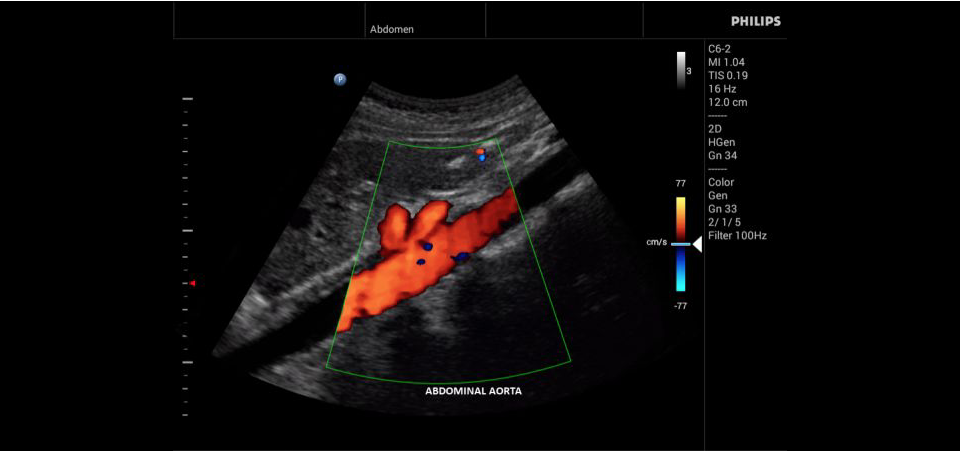

• Цветное допплеровское картирование

• Конвексный УЗИ датчик Philips C9-4v

• Конвексный УЗИ датчик Philips С6-2